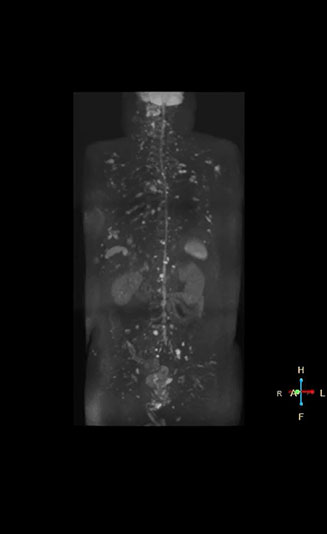

“The DWIBS sequence’s value in oncology cases is due to the high contrast it creates between lesions and surrounding tissue. Whole body DWI is requested by physicians who need to clarify TNM staging or determine therapeutic strategies, oncologists in need of diagnosis or follow-up scans, surgeons who need to see the presence of distant lesions that are sometimes difficult to detect by CT before surgery, and urologists for the evaluation of bone lesions, and the effect of chemotherapy and radiotherapy.”

Radiologist Hiroshi Nobusawa, MD, PhD, explains that the coronal DWIBS protocol for whole body DWI is excellent for visualizing lesions in oncology patients. “About 90% of the DWIBS exams are done in this type of patients. The remainder of DWIBS exams are performed to gain information in cases of fevers of unknown origin,” he says. in image acquisition and postprocessing algorithms.”“mDIXON TSE sequences allow simultaneous characterization of morphological changes from the in-phase T2-weighted images and visualization of edematous changes, thanks to the water T2-weighted images from the same acquisition. Anatomical and morphological considerations could be a partial or complete ligament tear, a bony avulsion or hematoma.” “For soft tissue assessment mDIXON brings similar benefits. For example in one T2-weighted mDIXON TSE acquisition, having the multiple contrasts helps us assess abnormalities in peripheral nerves fascicles, which may be due to anatomical or inflammatory changes..” “In peripheral joints, we get good image quality in difficult areas with mDIXON TSE. Fat suppressed images appear homogeneous over the entire image, even with large coverage at 3.0T – for instance in scapular or hip girdles – or in the bearing areas or around metal prostheses*, where fat suppression is often deficient with STIR or spectral fat suppression, causing diagnostic difficulties. If a diagnostic image is right the first time, we don’t need to repeat or add a sequence.” “mDIXON TSE sequences allow simultaneous characterization of morphological changes from the in-phase T2-weighted images and visualization of edematous changes, thanks to the water T2-weighted images from the same acquisition. Anatomical and morphological considerations could be a partial or complete ligament tear, a bony avulsion or hematoma.” “For soft tissue assessment mDIXON brings similar benefits. For example in one T2-weighted mDIXON TSE acquisition, having the multiple contrasts helps us assess abnormalities in peripheral nerves fascicles, which may be due to anatomical or inflammatory changes..”